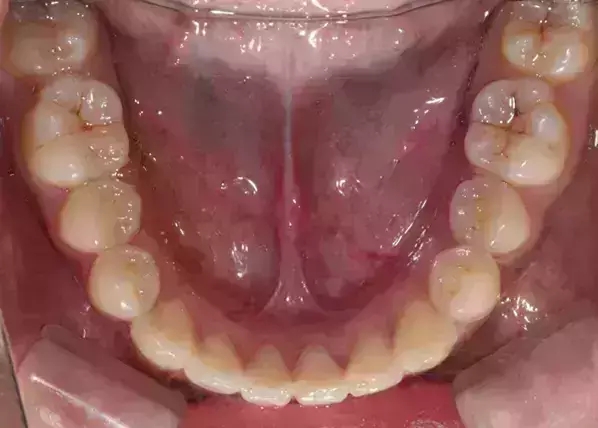

Damon 病例分享:安氏 II 類二分類露齦笑的矯治(董一磊)

治療前后對比